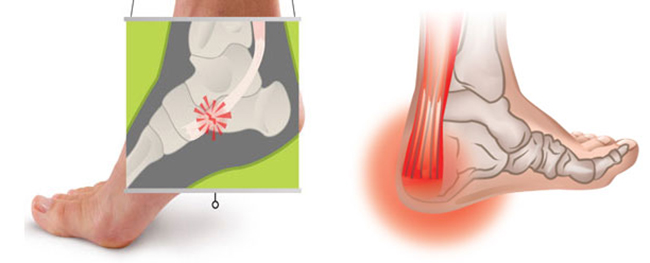

Тендинит Ахиллова сухожилия: симптомы и лечение

Раздел: Картинки на заметку